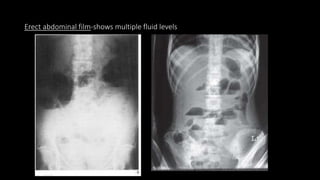

Erect abdominal film-shows multiple fluid levels

Erect abdominal film-showsmultiple fluid levels